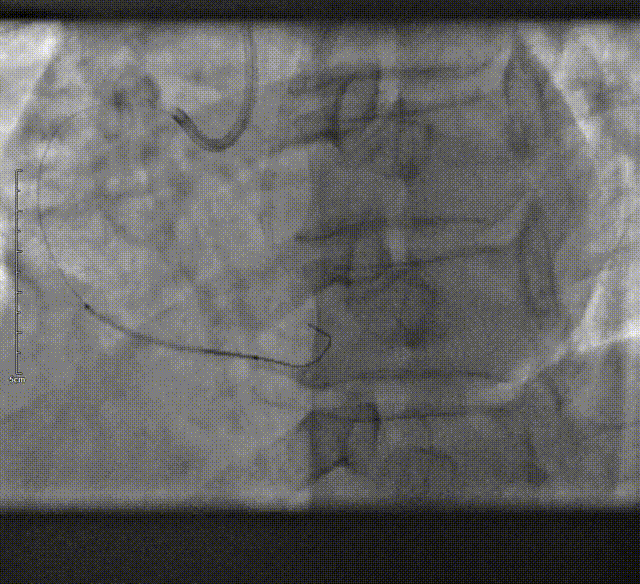

LM未见明显狭窄,LAD近段至远段支架内无再狭窄,支架出口狭窄95%,LCX近段狭窄75%,远段次全闭塞,RCA近中段段狭窄80-95%,远段次全闭塞。